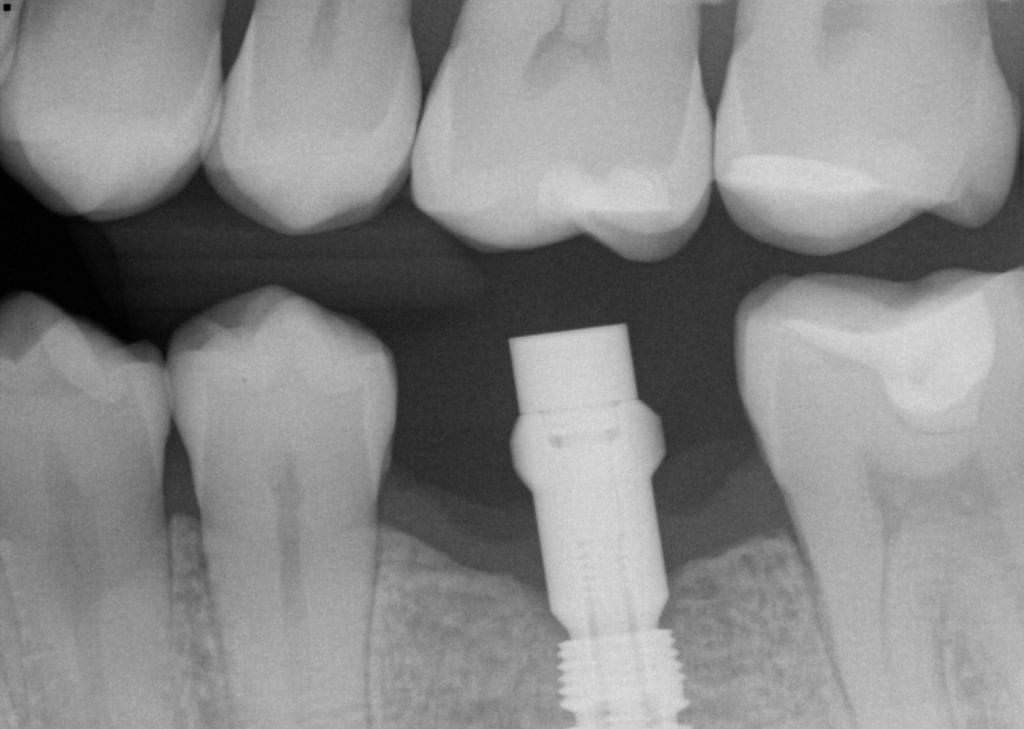

Importance of taking a radiograph to verify accurate interface of the Crown Not Fully Seated Decay is arguably the most common problem associated with dental crowns. Remove the provisional crown and clean the prep of cement and debris. Making a crown fit perfectly between adjacent teeth. open margins may be a result of the crown not seating fully on the tooth. With a little detective work, your dentist may be able. An ideal crown. Crown Not Fully Seated.

From www.caringdentists.com